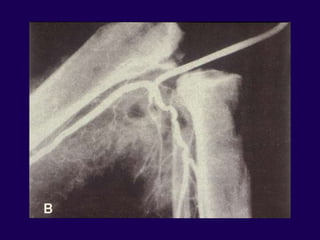

Infection – Work-Up

l Wound History

l Physical Exam

l Serial Radiographs

l Lab/sed rate/CRP

l Bone scan / Indium scan

Complications in Arthroplasty

Infection

Arthrocentesis

l Cell count

l Diff > 25,000 pmn

l Protein – high

l Glucose – low